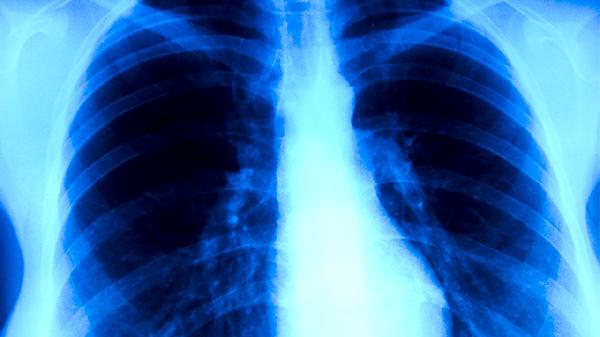

胸膜受累的耐药肺结核患者会出现针刺样胸痛,深呼吸或咳嗽时加重。胸痛与胸膜炎症、粘连或包裹性积液有关,普通镇痛药如布洛芬缓释胶囊难以缓解。胸部X线可能显示胸膜增厚或钙化,需通过胸腔积液检查排除合并感染。治疗上需加用左氧氟沙星片等氟喹诺酮类药物。